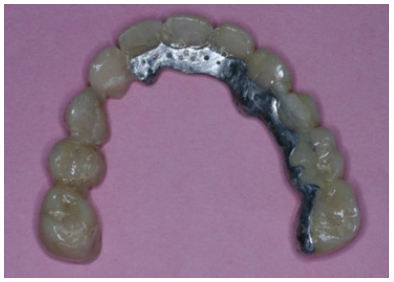

The final preparations were observed in two study casts to improve the parallelism and ensure accurate path of the insertion for the final prostheses. Final preparations and relining of the provisional restorations followed. Final impressions were performed using polyvinyl-siloxane (Aquasil, Dentsply, Germany) with the two-step double mixing technique (stock tray, double cord technique) in the maxilla. Mandibular impression was performed with an open tray technique combining implant and teeth abutments with polyether material (Impregum, 3M, USA). In next appointment the accuracy of final casts was examined and jaw relation recordings were performed. The position of maxillary cast was transferred with a Whip-Mix face bow and centric relation (CR) was registered with a custom made acrylic Lucia jig (anterior deprogrammer) and an implant retained base plate in the mandible to ensure accurate registration. Dental and implant abutments metal try-in were completed in two steps (Figure 16). After thorough verification of accuracy of fit and jaw registrations, ceramic veneering was checked for proper occlusion (Figure 17,18). Finally all restorations were cemented with adhesive resin cement (Panavia F2.0, Kuraray, Japan), except for the implant restorations which were cemented with a provisional cement (Temp-bond, Kerr, Germany).

Figure 18: Final restorations occlusal view of the mandible.